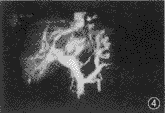

图3肝多发血管瘤。清楚显示门静脉主干和肝内各级分支,走向自然,管径粗细均匀;各血管瘤(团块状高密度影)均可准确定位

1.良性病变的CTP表现:本组资料内3例囊肿、1例结节性肉芽肿(FNH)、5例血管瘤及2例肝脓疡均可清楚显示病灶与周围血管的关系,门静脉走向自然,只有在病灶较大时对其有推移,但血管边缘清晰,无受侵或栓子形成(图3)。